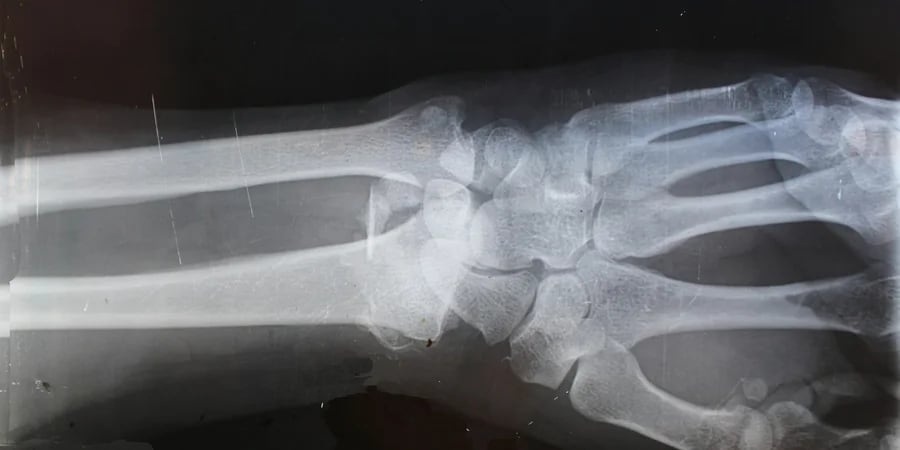

У сучасній травматології складні переломи або видалення кісткових пухлин зазвичай вимагають встановлення титанових пластин або болісної пересадки власної кісткової тканини пацієнта з іншої частини тіла. Швейцарські вчені запропонували революційну альтернативу – інноваційний біосумісний гідрогель, який працює як тимчасові «будівельні риштування» для нашого організму.

Цей матеріал за своєю фізичною консистенцією нагадує дуже щільне желе. Хірурги заповнюють ним пошкоджену ділянку, після чого відбувається диво клітинної біології. Спеціально розроблена молекулярна структура гелю приваблює остеобласти – клітини, що формують кістку. Вони активно заселяють цей каркас, починають виділяти колаген і нарощувати справжню кісткову тканину. У міру того як росте нова кістка, гідрогель повністю і безслідно розчиняється.

Після успішних лабораторних досліджень команда готується до клінічних випробувань, мета яких – назавжди позбавити пацієнтів потреби жити з металевими імплантами в тілі.